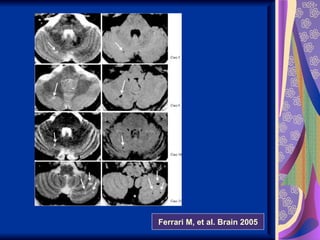

Migraine and Stroke Womenunder 45 Posterior circulation strokes and white matter lesions more likely in MWA and high attack frequency of migraine than controls Women 45 years and older MWA twice as likely to develop ischemic stroke and MI over 10 years of follow-up

Ferrari M, etal. Brain 2005